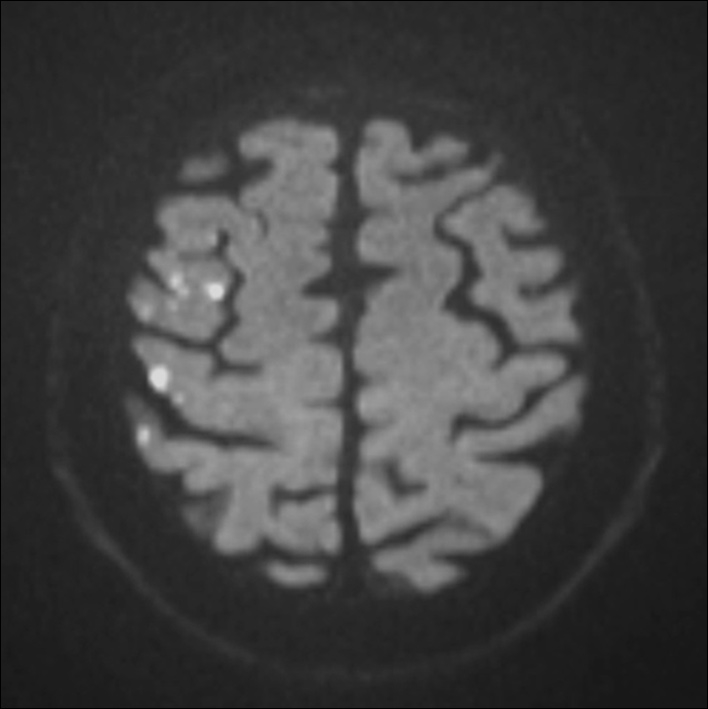

Figure 3

Diffusion weighted MRI of a patient following stenting of the right carotid artery in the MRI substudy of the International Carotid Stenting Study. Multiple hyperintense signals representing acute ischaemic lesions in the territory of the right middle cerebral artery are present. The patient did not experience any symptoms. © Department of Radiology, University Hospital Basel. Reprinted with kind permission.

In carotid revascularisation, cerebral ischaemia may occur without overt symptoms of stroke or TIA. Transcranial Doppler sonography and diffusion-weighted brain imaging (DWI), a magnetic resonance sequence which is highly specific and sensitive to acute cerebral ischaemia, have been used to detect subclinical embolic events in CAS and CEA. A systematic review of non-randomised studies using DWI before and after treatment showed that an average of 37% of patients had new ischaemic lesions after CAS, compared with 10% of patients after CEA [21]. Within ICSS, a multi-centre prospective substudy investigated 124 patients randomised to CAS and 107 patients randomised to CEA with DWI before and after treatment [22]. 50% of CAS patients and 17% of CEA patients had new ischaemic lesions on DWI after treatment (OR 5.21, 95% CI 2.78–9.79, p <0.0001; fig. 3). Since assessment of MRI could be done without knowledge of the allocated treatment, these results argued against the presence of bias explaining the observed differences in rates of clinically manifest strokes. Furthermore, the use of DWI allowed detecting differences between treatments which were consistent with the clinical outcomes of the main trial in only a fraction of the study population. Therefore, DWI may potentially serve as a surrogate outcome measure in future pilot studies evaluating new treatment strategies or investigating disease mechanisms [21].